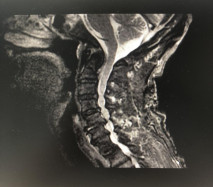

(术前拍片)

在完善了各项相关检查后,张阿伯被诊断为:颈部脊髓损伤,不完全瘫痪及全身多处骨折,我院脊柱科主任戈才华建议其入院并接受颈后路颈椎融合手术。